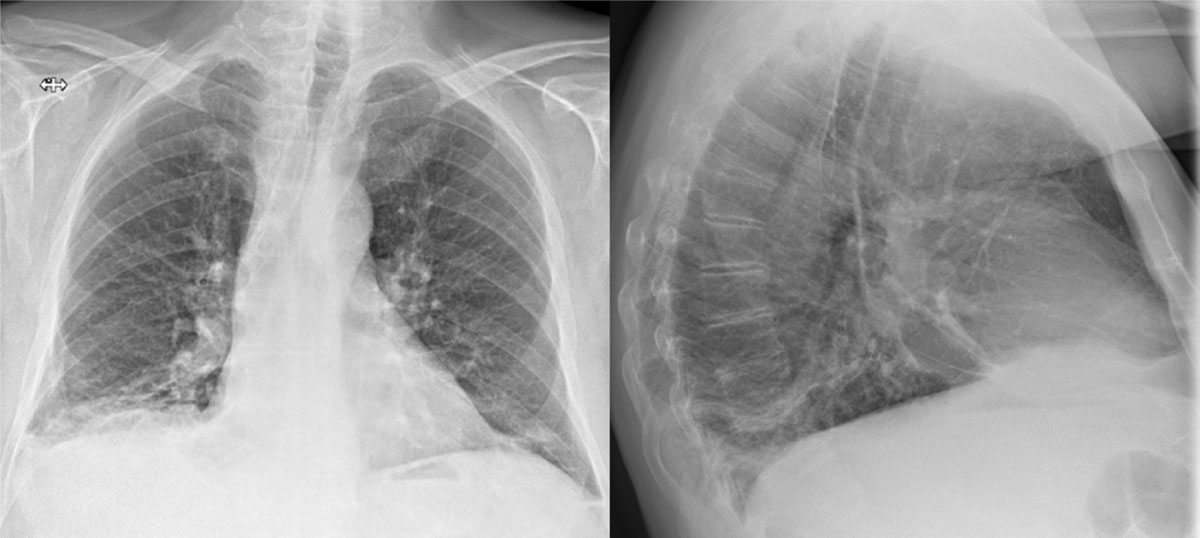

An 80-year-old man with a prior history of chronic lymphocytic leukaemia, presented to the emergency room with recurring fever, dyspnoea, cough, and bibasilar crackles. Two weeks prior, he had been admitted for a right lower lobe (RLL) pneumonia. Further investigation showed high CRP (180 mg/L) and lymphocytic leucocytosis (115.000/µL). Initial chest X-ray (CXR) showed increased pleural fluid on the right and several dense strands (Figure 1). The patient was treated for pneumonia using antibiotics with a subsequent decrease in CRP.

Figure 1

CXR with increased pleural fluid at the right lung basis and several dense strands.

In retrospect, we can identify an enlarged right inferior hilum (Fleischner sign) with adjoining tapering of the pulmonary vessel (knuckle sign) on the initial CXR (Figure 1) [15]. These signs often coincide and are highly specific for PE, yet of low sensitivity. Other examples are the Westermark sign or Hampton-hump [156], whilst not clearly visible in this case. The initial diagnosis in our patient was delayed due to the recent history of pneumonia and since D-dimers were not measured. Luckily, when chest CT was finally performed, presence of the atoll sign in the subpleural, dorsobasal part of the RLL was quickly picked up as a possible lung infarction and CT angiography was advised, confirming the diagnosis.